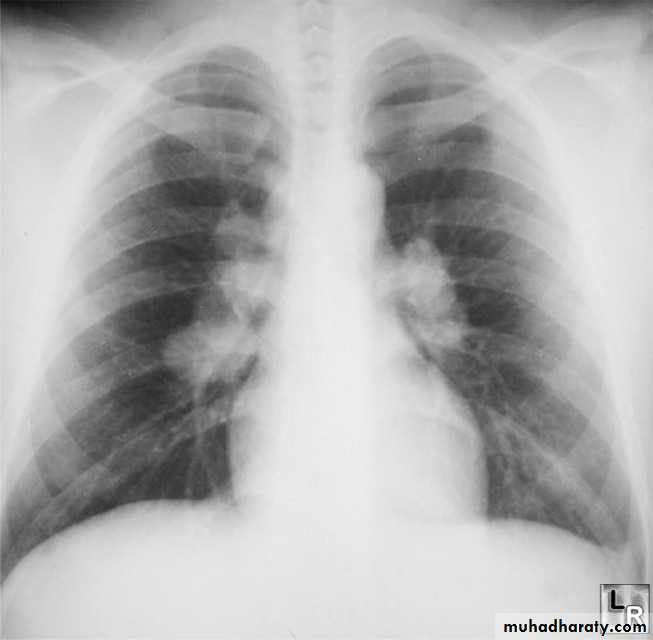

Lymphoma

is a malignancy arising from lymphocytes or lymphoblasts. Lymphoma can be restricted to the lymphatic system or can arise as extra nodal disease. This, along with variable aggressiveness results in a diverse imaging appearance.

Nodal disease

Hodgkin's disease is usually almost entirely confined to the lymph nodes.

Extra nodal disease

Extra nodal HD although uncommon may be found in any organ system, either as a primary manifestation or as dissemination of systemic disease.

Hodgkin lymphoma of te middle mediastinum